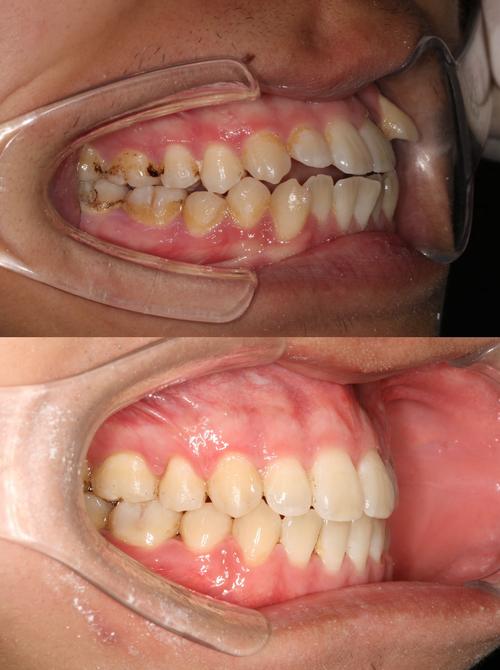

牙齿正畸的治疗流程通常包括初诊检查、方案设计、矫治实施、保持四个阶段,初诊时,医生会通过临床检查、影像学检查(如X线头颅侧位片、曲面断层片)及数字化扫描等方式收集患者口腔数据;方案设计阶段,结合患者的主观需求与客观检查结果,制定个性化矫治计划,并通过3D动画向患者展示预期效果;矫治实施过程中,患者需定期复诊(通常为4-6周一次),医生根据牙齿移动情况调整矫治力;拆除矫治器后,需佩戴保持器以维持疗效,防止复发,整个治疗周期因错颌类型复杂程度不同,通常为1.5-3年,期间患者需与医生密切配合,注意口腔卫生维护,避免食用过硬、过黏食物。

正畸期间的口腔卫生维护至关重要,由于托槽、弓丝等附件容易存留食物残渣,若清洁不当易引发龋齿、牙龈炎等问题,建议患者使用正畸专用牙刷(如V形牙刷)、牙间刷、冲牙器等工具,配合含氟牙膏进行清洁,每次进食后及时漱口并刷牙;避免啃咬硬物(如坚果、骨头)、嚼口香糖等,防止托槽脱落,部分患者在治疗初期可能出现牙齿酸痛、口腔黏膜溃疡等不适,通常在3-5天内缓解,若症状持续或加重,需及时复诊。